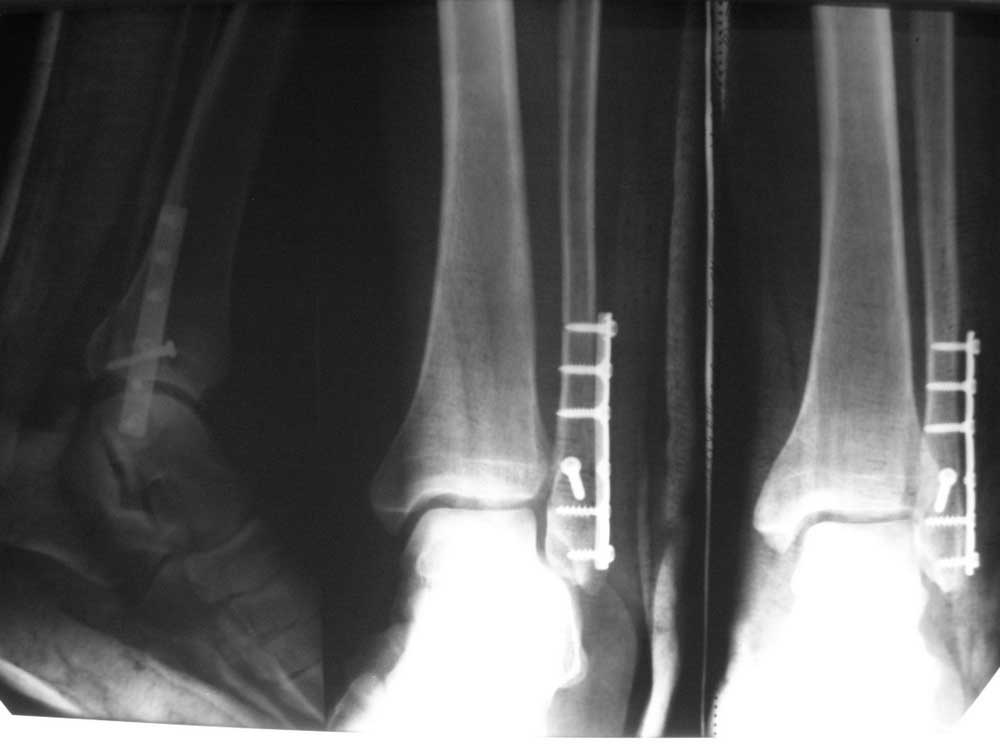

Пострадавший прооперирован 03.08.11. На послеоперационных снимках рентгенолог (зав. службой) описывает подвывих кнаружи. Врачи нашего отделения (заочный аспирант, кандидат наук и доктор со стажем 20 лет) этот подвывих не видим. По-поводу подвывиха на нас идет накат со стороны начмеда (больной- личный друг главы администрации района). Заведующий занял нейтральную позицию. Заранее благодарен!

На представленных рентгенограммах подвывиха нет. А рентгенолог, безусловно, неправ. Даже если и был бы минимальный подвывих, зачем его описывать. Видимо, у вас с ним не очень хороший контакт. Это плохо.

хорошая репозиция, подвывиха не видно. а гипс зачем?

Подвывиха здесь нет. Ширина суставной поверхности одинакова на всем протяжении.

Положение отломков правильное, таран стоит в правильном положении.

Подвывиха на предоставленных снимках нет, синтез достойный звания советского врача, но поверьте опыту раз пациент с осложненным анамнезом (глава администрации) то найдут все и спросят почему "какой-то" винт мимо пластины закрутили.

Насколько можно понять по снимкам- перелом чрезсиндесмозный и позиционный винт бы избавил от лишних вопросов.С другой стороны данных за подвывих здесь не наблюдается- снимки вполне можно переописать у другого рентгенолога.

Никогда не лечите знакомых, друзей знакомых и родных. Кстати,что впрочем не важно,ПОДВЫВИХА НЕТ РЕНТГЕНОЛОГИЧЕСКИ. То, что при данном переломе стопа уходит кнаружи, знает даже санитарка. Спасибо за работу.

На представленном снимке подвывиха однозначно нет.Но,по моему мнению,есть повреждение межберцового синдесмоза. Как только больной станет на ногу(да с таким весом)подвывих появится.Поэтому,нужно правильно побеседовать с пациентом и лечить гипсовой лонгетой,если уже поздно добавить 1-2позиционных винта.Удачи!

А так - на снимке компрессионный шуруп на малоберцовой находится на уровне суставной щели что доказывает перелом Weber II или (SER II). Наружноротационный перелом создает спиральную линию, которая начинается на месте прикрепления или ниже tibiafibular ligament. Поэтому не стоит драматизировать фиксацию, и обычно достаточной бывает фиксация латеральной пластиной, которая удержит частичный разрыв синдесмоза.

Насчет пластины - немного тонковата, и лежит спереди малоберцовой. Возможно проекционно, но там кажется перелом заднего края? Если так, можно было подождать с нагрузкой и оставить гипс на пару недель больше.